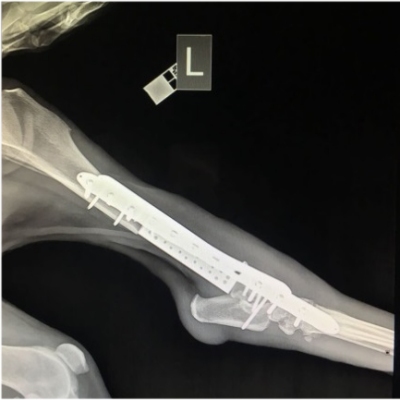

Uma prótese biomimética (que imita a estrutura óssea) e híbrida (feita de polietileno de ultra-alto peso molecular e liga de titânio) foi pela primeira vez implantada com sucesso em um animal de grande porte.

O protótipo experimental biomimético, similar em estrutura aos tecidos de um organismo vivo, foi implantado em um cão com osteossarcoma do fêmur.

Em apenas alguns dias, o animal voltou a andar e sua mobilidade será totalmente restaurada nos próximos meses, de acordo com as previsões da equipe da Universidade Nacional de Ciência e Tecnologia da Rússia.

"Nós realizamos com sucesso uma operação protética. O implante é durável, correspondendo ao peso do cão e ao tamanho do osso. Aqui, os resultados a longo prazo são mais importantes, para que o implante esteja acostumado e enraizado no osso. Nós podemos esperar progresso, mas leva tempo. Agora estamos observando o cão enquanto ele passa pela quimioterapia," disse Ilya Vilkovyskiy, coordenadora da equipe.